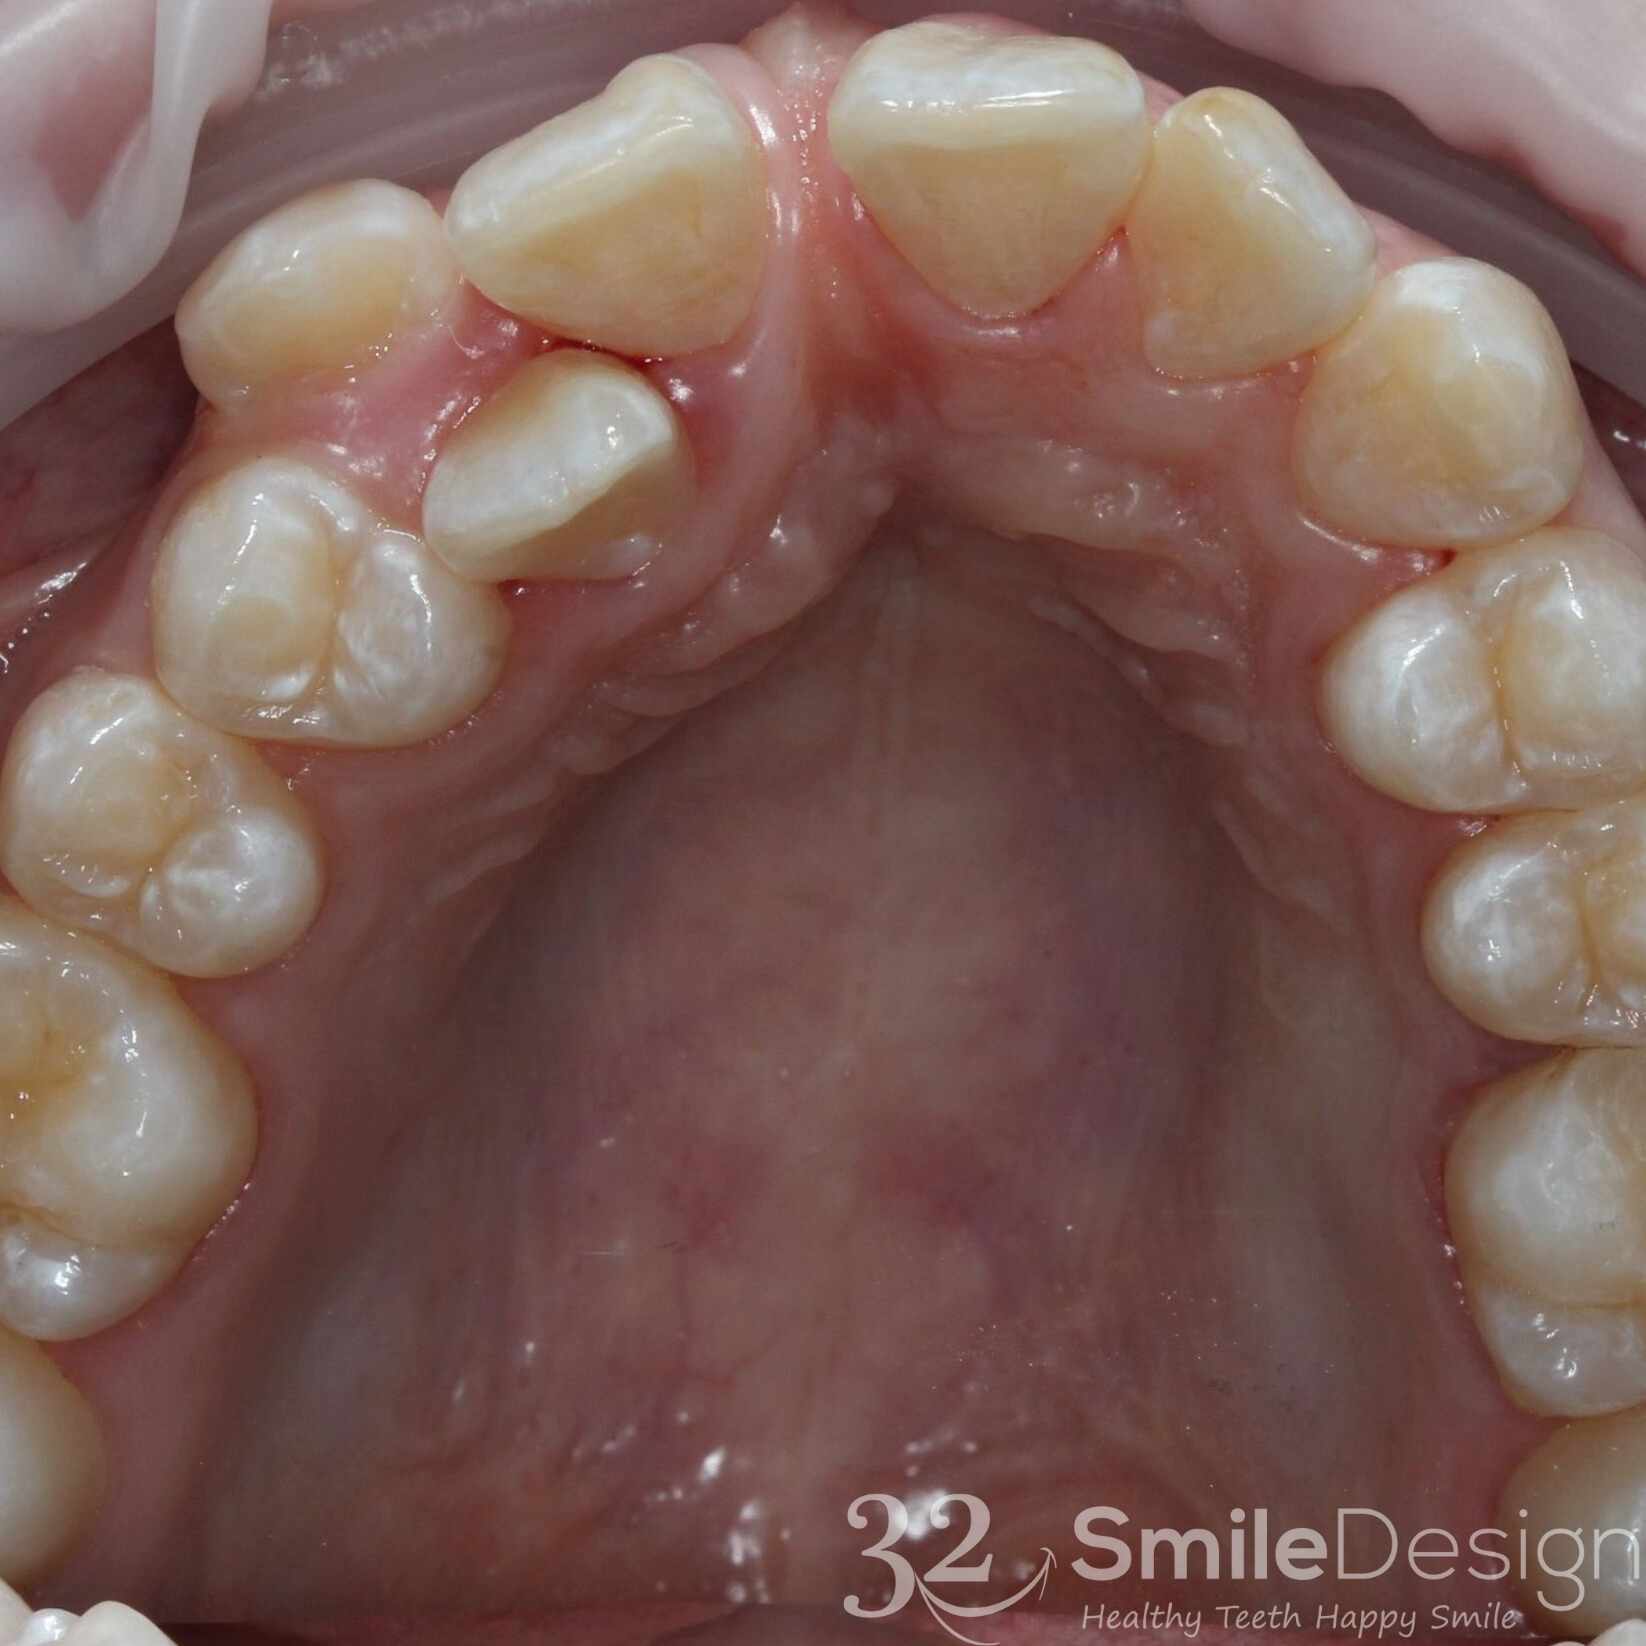

Lower Jaw - Before & After

Upper Jaw - Before & After

Lower Jaw - Before & After

Upper Jaw - Before & After

Lower Jaw - Before & After

Upper Jaw - Before & After

Lower Jaw - Before & After

Upper Jaw - Before & After

Lower Jaw - Before & After

Upper Jaw - Before & After

Lower Jaw - Before & After

Upper Jaw - Before & After

Upper Jaw - Before & After

Lower Jaw - Before & After